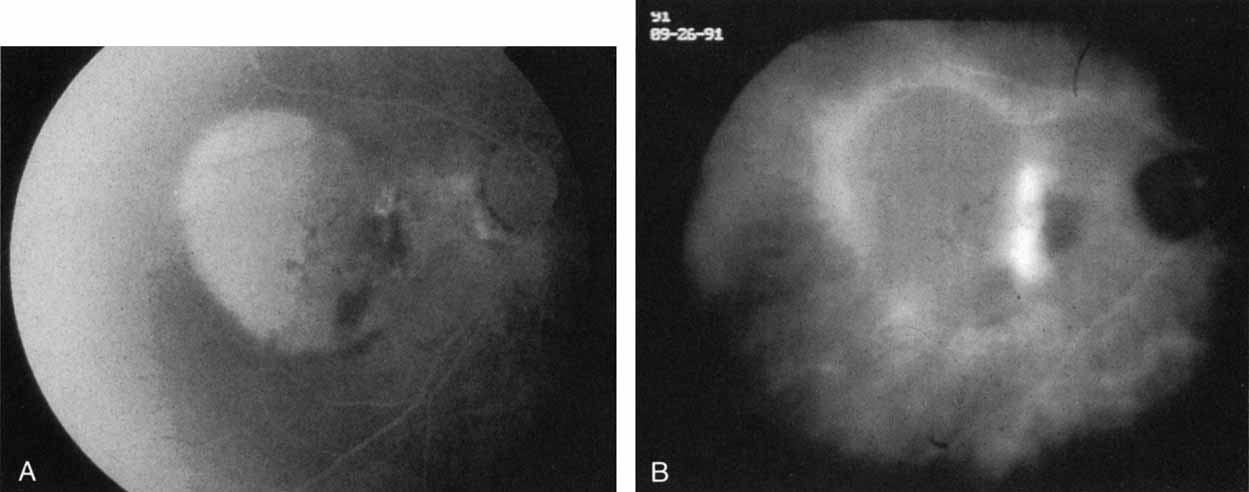

HARADA DISEASE

Harada disease, an inflammatory condition often affecting both eyes in young patients, is typified on fluorescein angiography by multiple focal areas of hypofluorescence early in the study, followed by late confluent leakage in the later phases (Fig. 17A, 17B, and 17C). With ICG angiography, multiple focal hypofluorescent spots are seen in the early phases, many more than were noted on the fluorescein study64,68 (Fig. 17D). The process extends further than the clinically or angiographically involved areas. The spots vary in size and density but appear to be well circumscribed. In the later phases of the ICG study, there is generalized hypofluorescence, with masking of the background choroidal fluorescence by the neurosensory detachment (Fig. 17E). This masking effect covers a large area, with inferior round margins confirming the gravitating nature of the neurosensory elevation. In addition, focal hyperfluorescent spots can be seen, possibly representing sites of active chorioretinal leakage or inflammation. In one patient, steroid therapy resulted in a marked resolution of clinical findings within 1 week.68 Repeat ICG angiography revealed a marked resolution of the hypofluorescent lesions as well as the hyperfluorescent spots. New areas of hypofluorescence did appear, the significance of which remains undetermined (Fig. 17E).

Fig. 17 Clinical photograph of a patient with Harada disease demonstrating multiple serous elevations of the retinal pigment epithelium with an overlying shallow neurosensory detachment. B. Early-phase fluorescein angiogram demonstrating hypofluorescent spots at the site of localized inflammation. C. Late-phase fluorescein study demonstrating hyperfluorescence in a confluent nature in the central macula. D. Early-phase indocyanine green (ICG) study demonstrating hypofluorescent spots in the central macular region. Note that the lesions are more numerous and more widely distributed than noted on clinical or fluorescein angiographic examination. E. Late-phase ICG study demonstrating extensive areas of confluent hypofluorescence. Note the curvilinear and gravitating nature of these hypofluorescent lesions, which are believed to represent blocked fluorescence from the shallow neurosensory detachment. Focal hyperfluorescent spots are noted within this region, which may represent areas of more active inflammation.